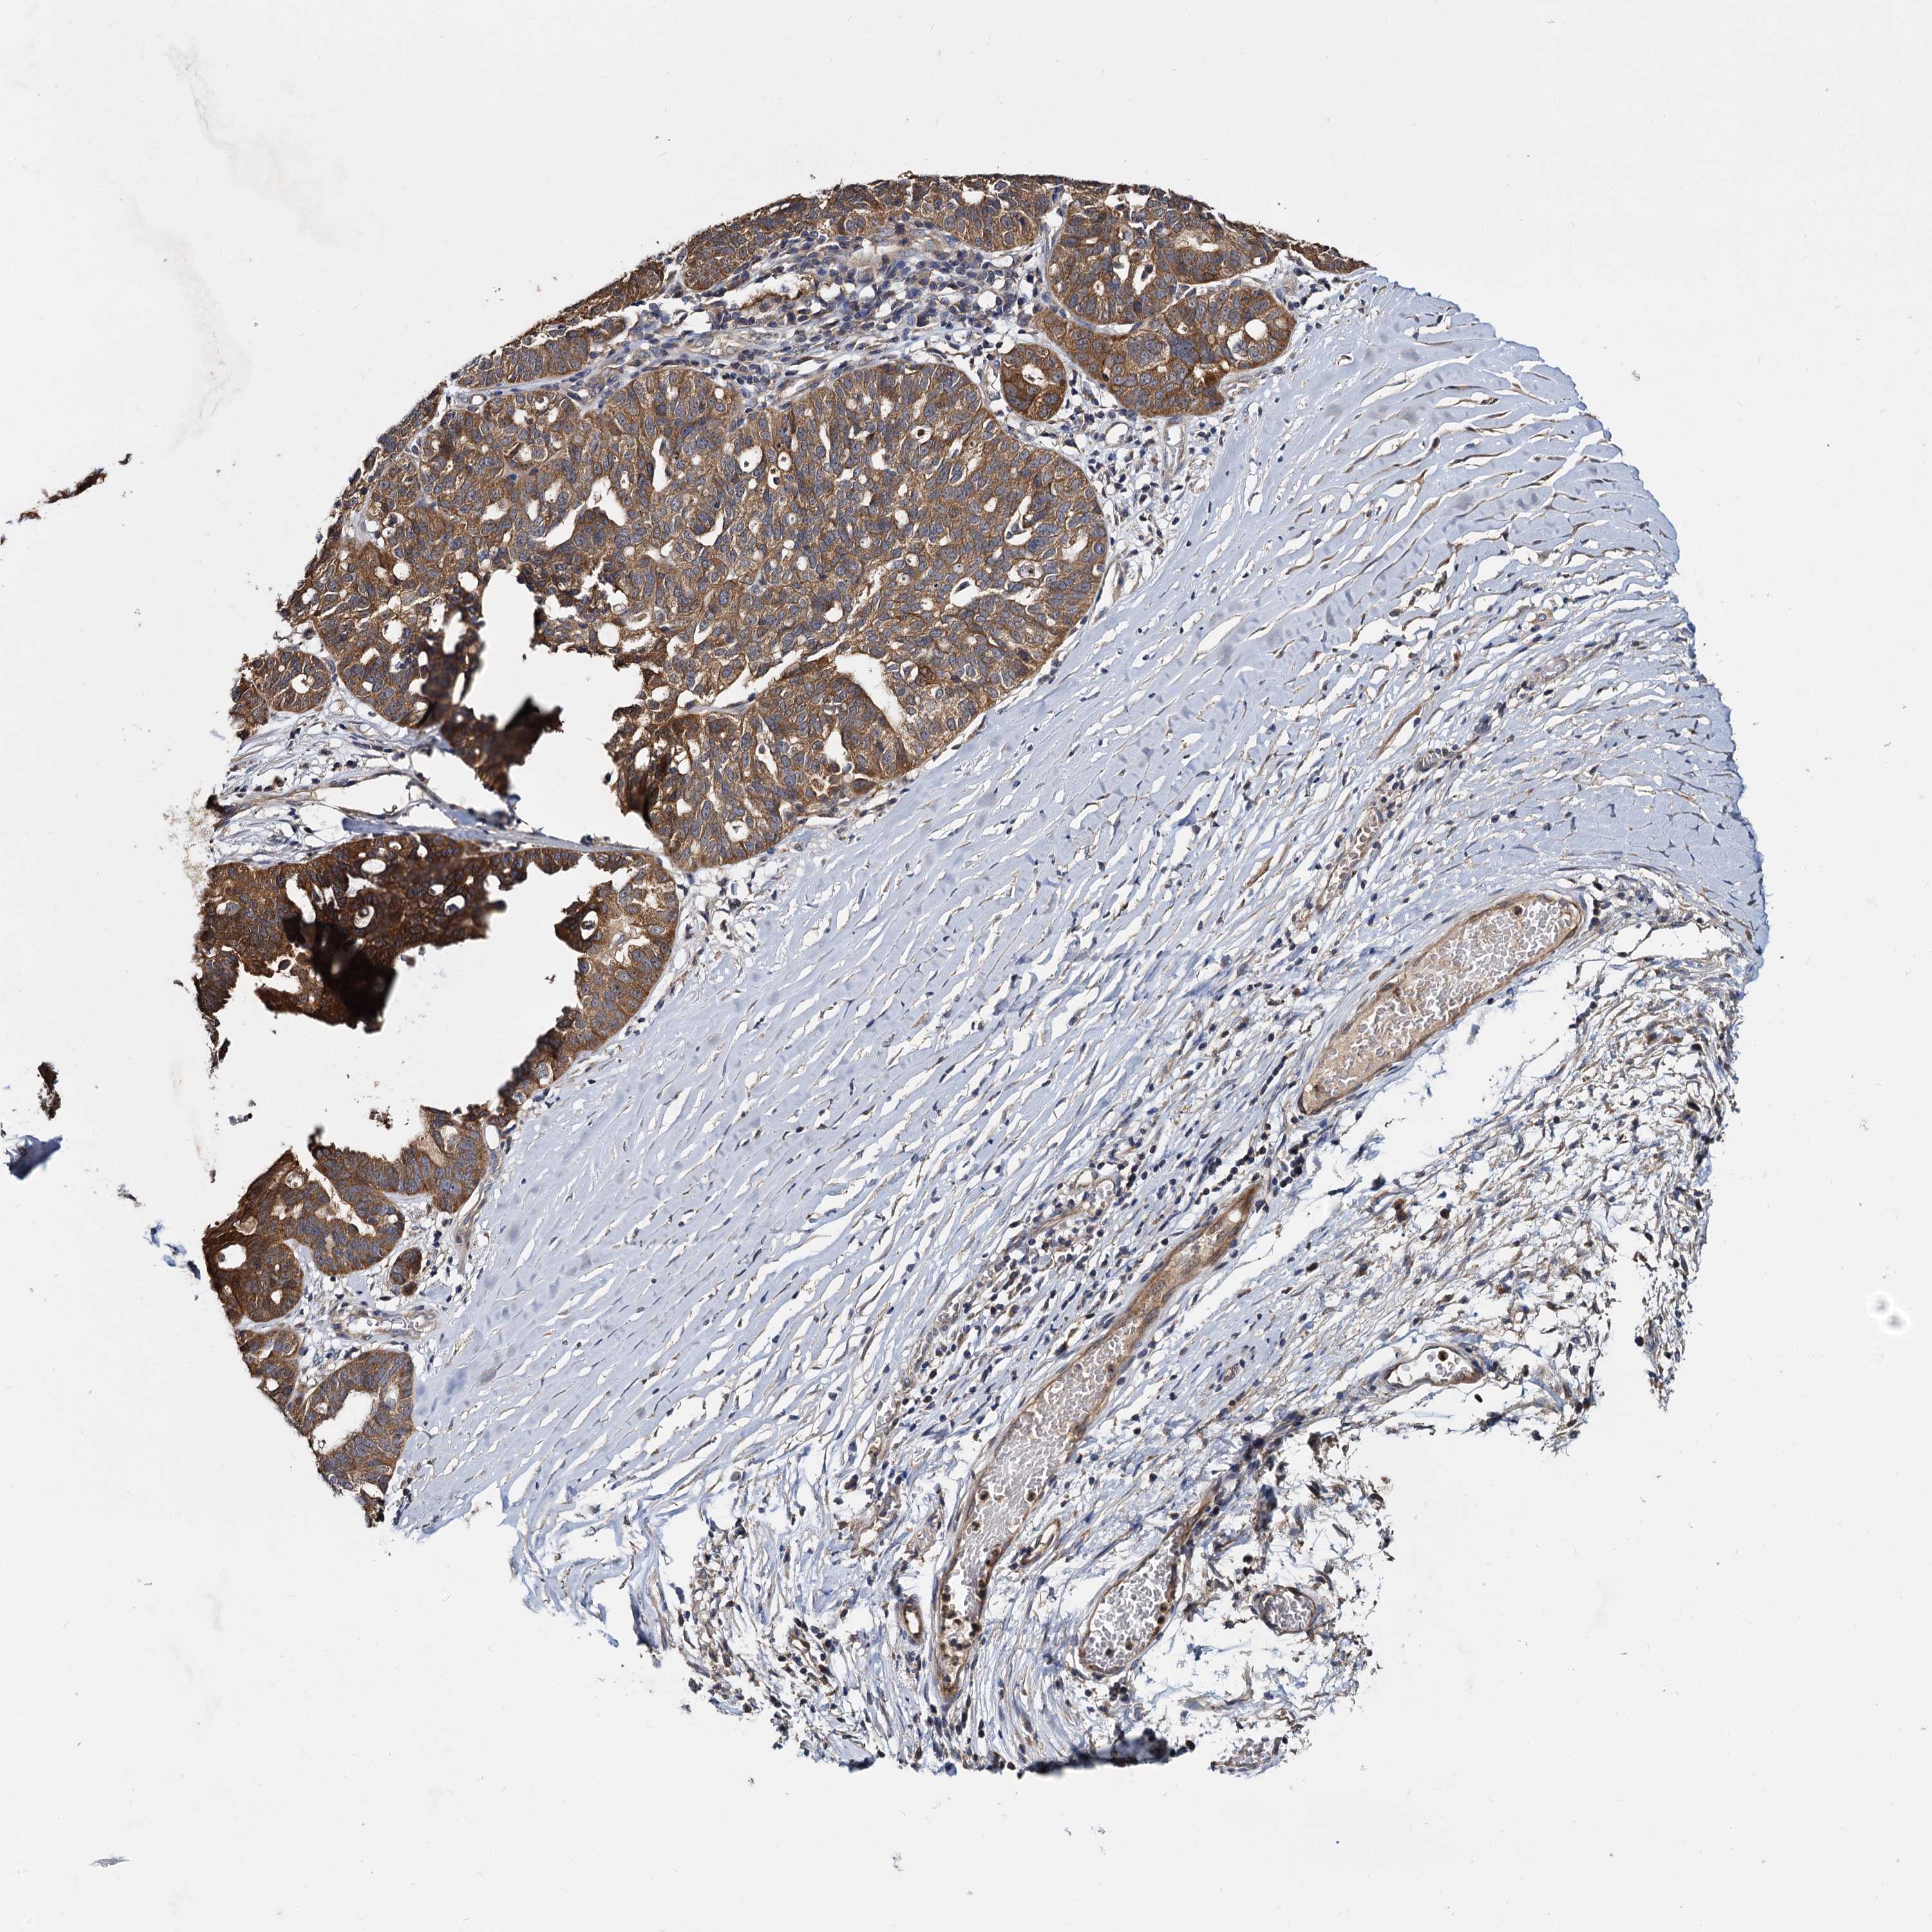

OVARIAN CANCER - Protein expressioni

A mouse-over function shows sample information and annotation data. Click on an image to view it in a full screen mode. Samples can be filtered based on level of antibody staining by selecting one or several of the following categories: high, medium, low and not detected. The assay and annotation is described here.

Note that samples used for immunohistochemistry by the Human Protein Atlas do not correspond to samples in the TCGA dataset.

Antibody stainingi

Antibody staining in the annotated cell types in the current human tissue is reported as not detected, low, medium, or high, based on conventional immunohistochemistry profiling in selected tissues. This score is based on the combination of the staining intensity and fraction of stained cells.

Each image is clickable and will lead to virtual microscopy that enables deeper exploration of all samples and also displays staining intensity scores, fraction scores and subcellular localization as well as patient and tissue information for each sample.

Antibody HPA039392

Antibody HPA040503

Staining

Cystadenocarcinoma, serous, NOS

Carcinoma, endometroid

Cystadenocarcinoma, mucinous, NOS

Carcinoma, NOS